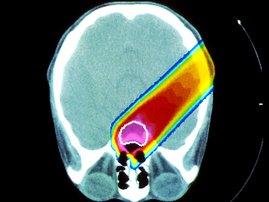

July 29, 2010 - Patients with deadly glioblastomas who received high doses of radiation on a portion of the brain that harbors neural stem cells had double the progression-free survival time as patients who had lower doses or no radiation targeting the area, a study from the Radiation Oncology Department at UCLA’s Jonsson Comprehensive Cancer Center has found.

Patients who underwent high doses of radiation that hit the stem cell niche experienced 15 months of progression-free survival, while patients receiving lower or no doses to this region experienced 7.2 months of progression-free survival, said Frank Pajonk, M.D., an associate professor of radiation oncology, a cancer center researcher and senior author of the study.

The retrospective study focused on the cases of 55 adult patients with grade three or grade four glioblastomas who received radiation at UCLA between February 2003 and May 2009. Pajonk said a prospective study is needed to confirm the results.

There is some evidence that many if not all cancers may spring from stem cells or progenitor cells that normally repair damage to the body, but that somehow become mutated and transform into cancer. In this case, Pajonk said the neural stem cell niche, called the periventricular region of the brain, may also be harboring stem cells that have transformed into brain cancer stem cells. However, the niche serves as a sort of safe harbor for the cancer stem cells, keeping them away from the site of the tumor but able to re-grow it once it’s removed and the malignant areas of the brain have been treated.

Pajonk theorizes that the brain cancer stem cells in the patients whose niches were irradiated with higher doses may have been damaged or eliminated, giving these patients more time before their cancer recurred.